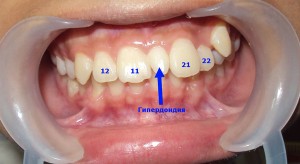

Гипердонтия — наличие сверхкомплектных зубов.

Клиническая картина. Сверхкомплектные зубы чаще локализуются в области верхних центральных и боковых резцов, реже — в области нижних резцов и других участков зубоальвеолярных дуг. В зависимости от их числа, расположения, а также от периода формирования прикуса эти зубы могут вызывать различные деформации зубных рядов. Величина и форма сверхкомплектных зубов бывают различными. Обычно такие зубы меньше соседних и имеют вид конуса, иногда их форма аналогична форме соседних зубов или атипична. Широкие коронки встречаются редко, в этих случаях они обычно бывают слившимися с комплектными. Ретинированные сверхкомплектные зубы чаще располагаются в области корней резцов и клыков, между ними, нередко бывают смещены в вестибулярном, оральном, латеральном направлениях, повернуты по оси, наклонены, расположены горизонтально. Иногда их коронки направлены в сторону верхушек корней соседних зубов, а корни обращены к вершине альвеолярного отростка, что способствует их стойкой ретенции. Сверхкомплектные зубы могут явиться причиной смещения соседних зубов, задержки их прорезывания, диастемы, искривления корней соседних зубов, поворотов их по оси, смещений и ретенции зубов, несоответствия размеров зубных рядов, нарушений прикуса.